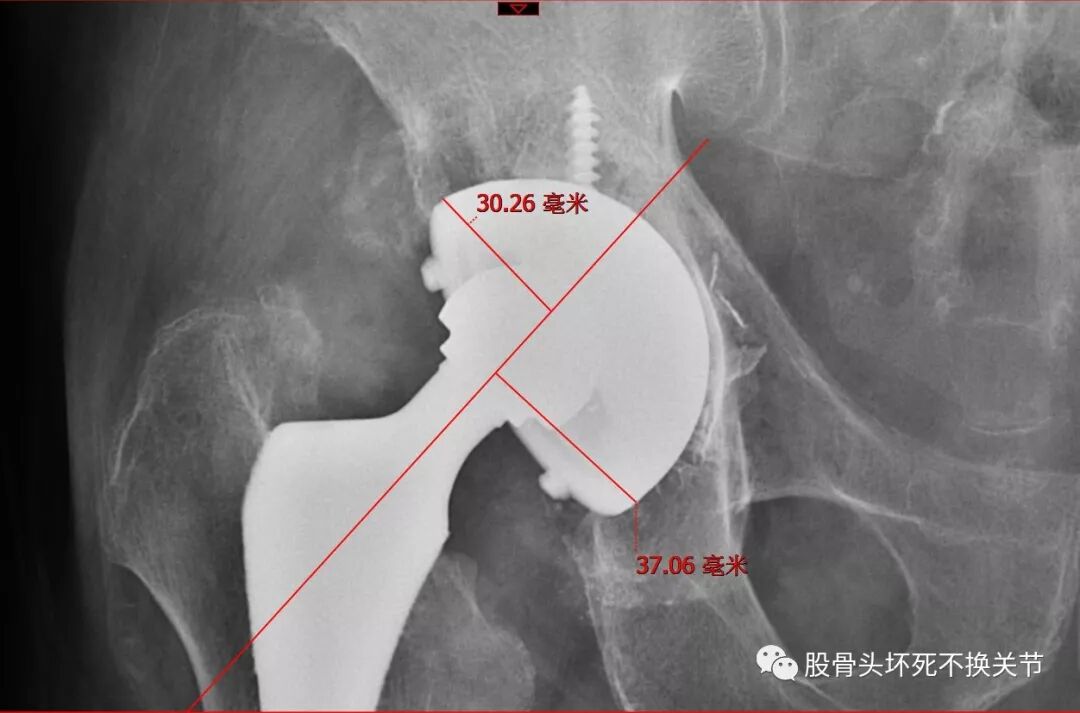

44岁,双侧全陶瓷关节置换